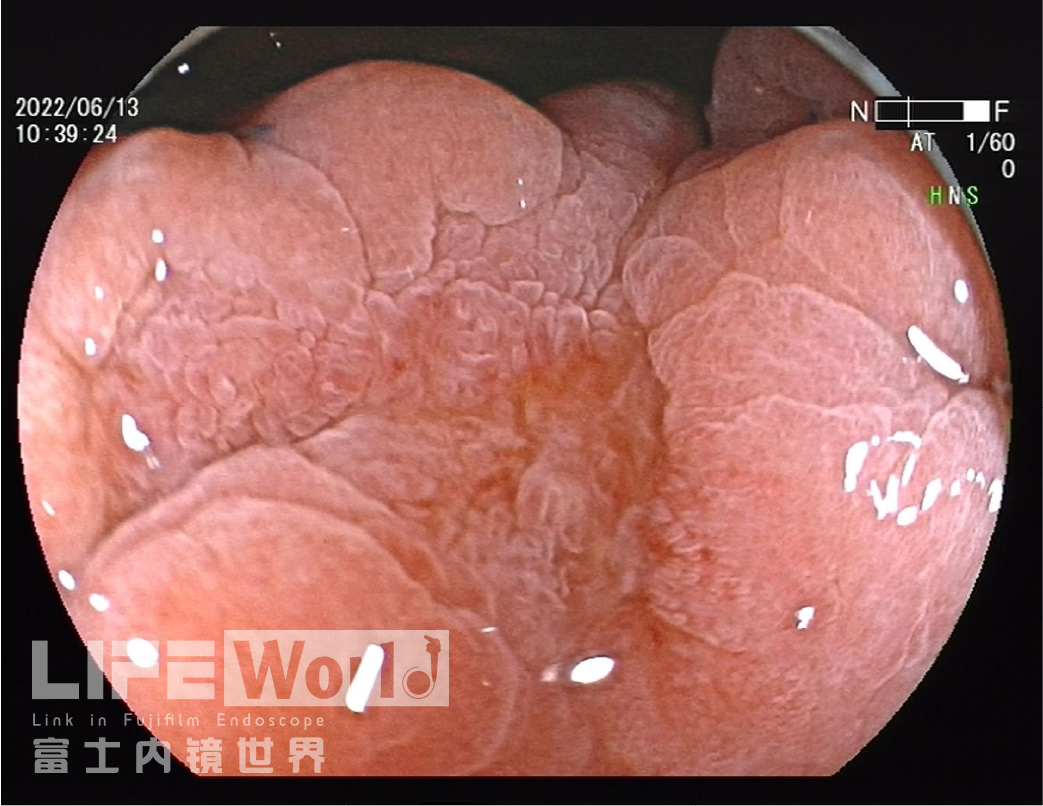

白光观察:胃体下段大弯侧可见一处中央凹陷的病变,色红,范围约1.2×0.6cm,周围黏膜集中、中断。

白光+LCI+BLI的对比观察。

BLI模式低倍放大观察,可清晰的勾勒出病变的范围,病变的口侧端表面微结构的异型性明显,考虑为癌灶,病变的肛侧端异型性不明显,考虑为上皮内瘤变。

该病变位于胃体下部大弯侧,病变大体分型为IIc型,病灶较小,有时候受皱襞影响不易发现,注气不充分时易漏诊,白光下给出了远景、中景及近景照片,并通过气体量的变化展现了不同注气状态下的病变形态,病变有皱襞集中、中断,未见皱襞融合现象,部分区域色泽发红,另外对病变肛侧端微小的粘膜变化也没放过,观察的很仔细,留图很规范。

1、白光下,病变位于胃体下部大弯,呈0-Ⅱc型的浅表凹陷病变,病变区域有皱襞的中断,这种改变多见于溃疡修复及低分化/印戒细胞癌。充分注气可以看到,皱襞中断处没有断崖式凹陷及末端膨大、分支,充气、吸气图像看病变区域蠕动良好,可以暂不考虑低分化/印戒细胞癌,病变浸润深度应局限在黏膜内或黏膜下浅层;